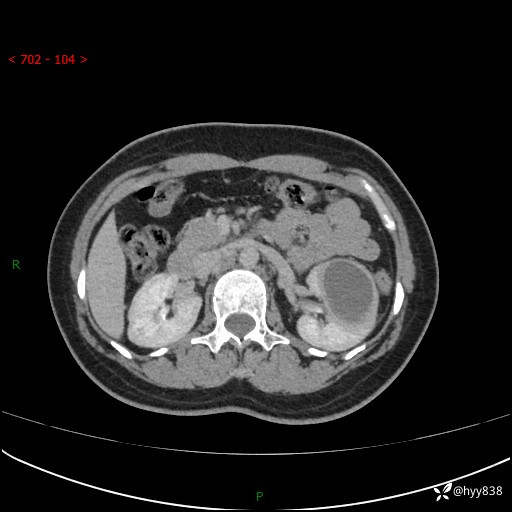

现病史:患者于1周前因左侧腰腹部间断胀痛不适,无恶心呕吐,无明显肉眼血尿,无畏寒发热,无尿频尿急,起病初,患者来我院就诊,查CT提示左肾低密度影,外周血提示:白细胞11.25*10^9/L.行抗感染治疗后未见明显好转,06-18泌尿系增强CT提示左肾类圆形低密度占位(脓肿?肿瘤?),大小:4.0*3.2cm,为求进一步治疗,门诊以“左肾占位”收住我科。 起病以来,患者精神佳,饮食、睡眠良好,大小便正常,体力体重无明显变化。

双肾CT平扫+增强